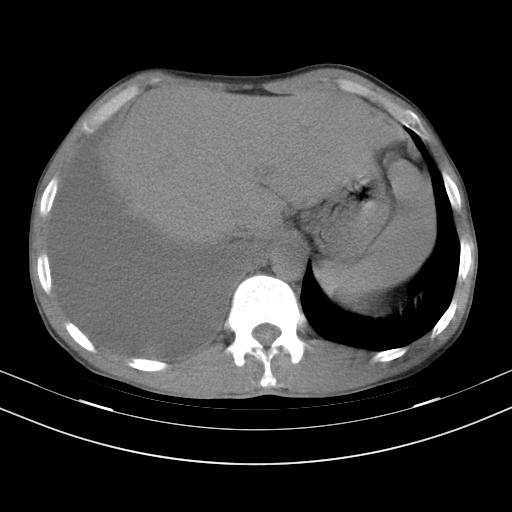

男性,44岁,结核病史多年。现胸闷气短,咳嗽,偶咳血。

右侧胸腔积液

右肺下叶不张

双肺多发结节影最分空洞形成考虑占位不除外结核

双肺陈旧性病变

1、右侧大量胸腔积液伴右肺压缩性膨胀不全,建议抽液治疗后复查 2、两肺继发性tb伴空洞形成。

1)两肺继发性肺结核伴空洞形成,左肺多发性结核球。2)右侧大量胸腔积液伴右肺部分膨胀不全。3)纵隔淋巴结肿大。

1,双肺多发结节 并空洞影改变, 左侧胸腔积液并部分包裹, 结合原病史首先考虑结核. 但也不除外其它.

2,左侧有一根肋骨陈旧性骨折? 建议追查 .

吉大一院胸水抽检结果:结核性胸水